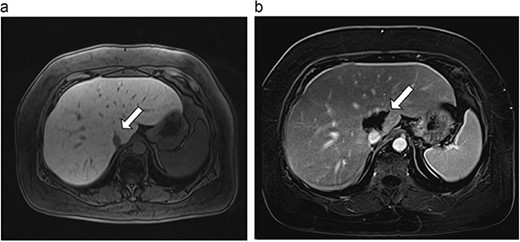

(a) Pre-ablation MRI demonstrates 6 mm lesion in caudate lobe of liver. (b) Post-ablation MRI (18 days postoperatively) demonstrates 40.4 mm complete ablation site in caudate lobe of liver.

| 1 (3a,b) | 61, F | Colon adenocarcinoma | 6-month FOLFOX | 1 | Laparoscopic microwave ablation | 6 | 40.4 | 34.4 | 10 | No |